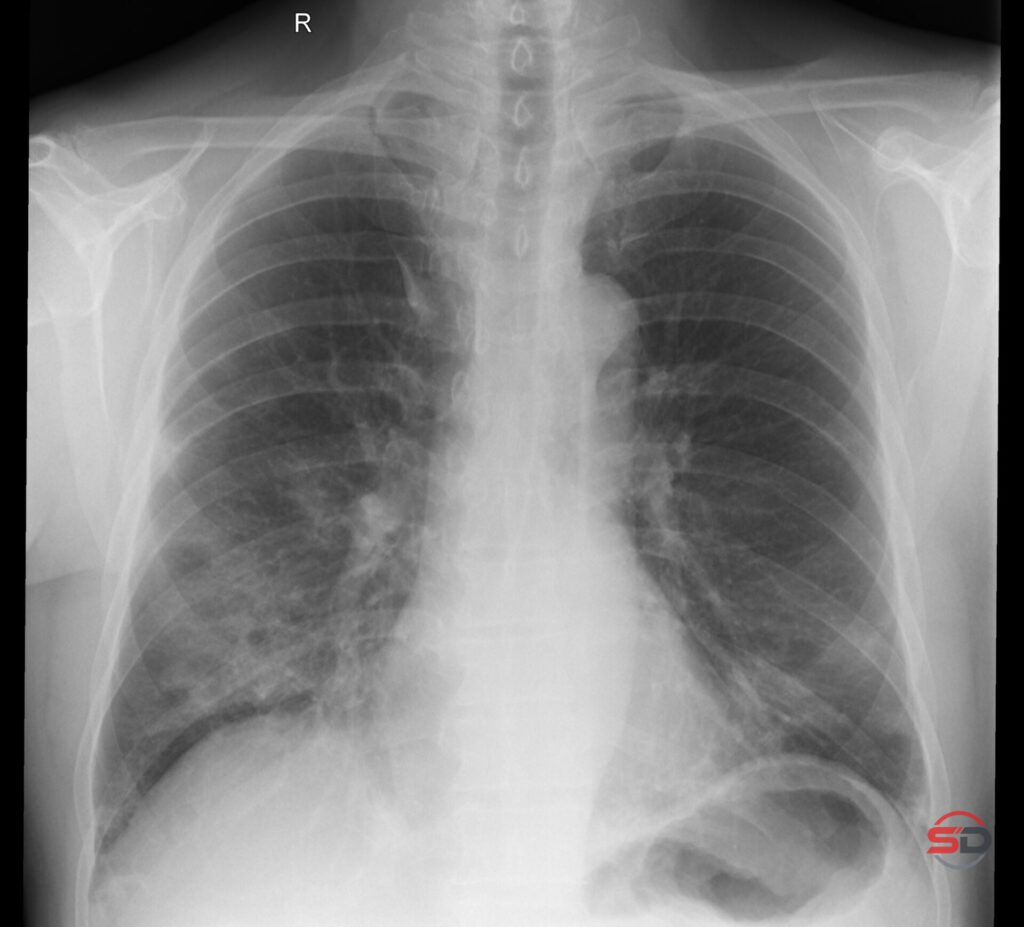

Organisierende Pneumonie Röntgenbild – OP/COP erkennen

Die organisierende Pneumonie im Röntgenbild – was darf man sagen, was nicht? Die organisierende Pneumonie (OP) ist eine entzündliche Lungenerkrankung, […]